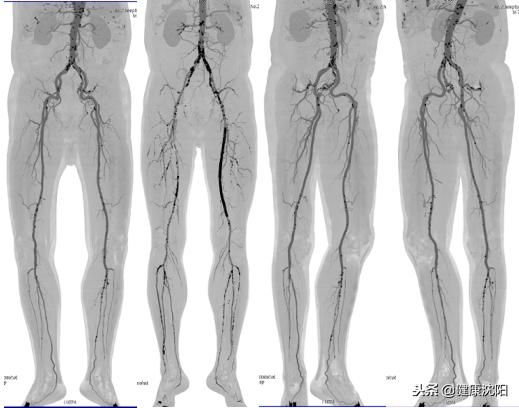

显示腹主动脉及双侧下肢血管影像与骨骼影像VR主次重叠显示

双下肢血管MIP仿DSA影像,可以显示钙化及支架影像

ghl:显示下肢血管曲面、拉直影像